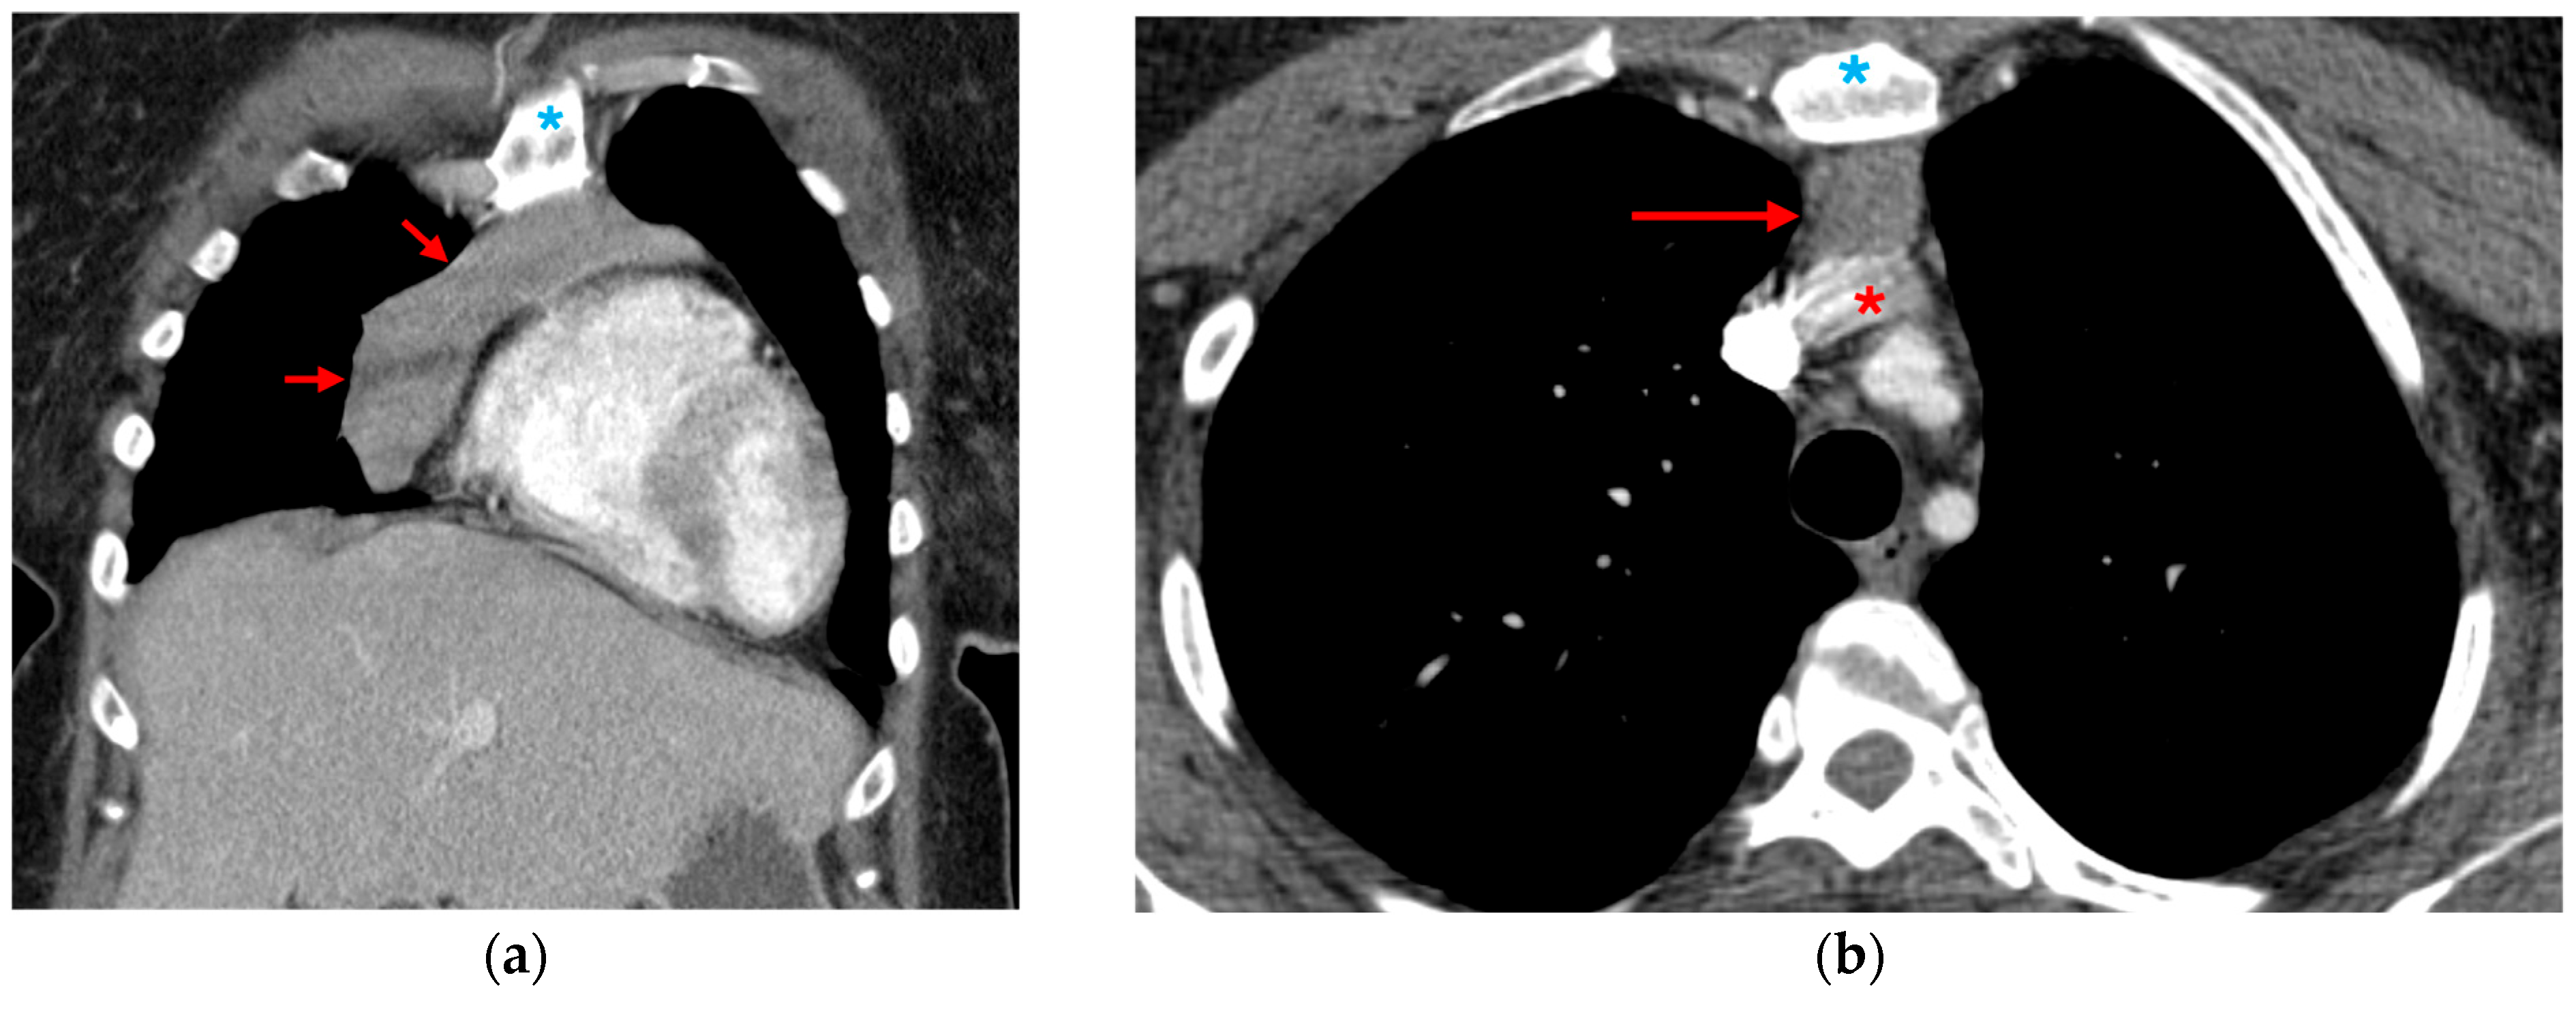

3.1.1. Direct Signs of Aortic Injury

3.1.2. Indirect Signs of Aortic Injury

3.1.3. Mimics and Anatomic Variations